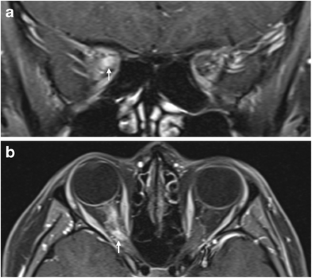

Fig. 1